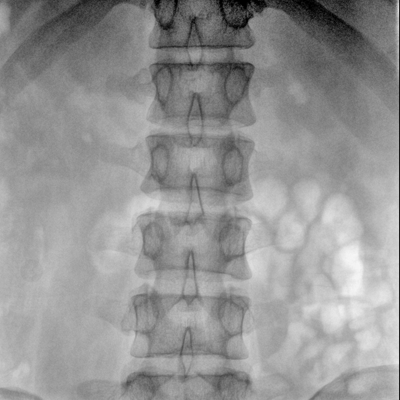

可用于常規(guī)的外周血管介入手術(shù),設(shè)備的移動性好,對手術(shù)室空間要求低,可滿足長時間X光透視的需求,且增加了獨特的血管影像處理功能,是開展介入手術(shù)的理想設(shè)備。

優(yōu)質(zhì)平板探測器、可靈活升降調(diào)節(jié)SID、獨特圖像處理系統(tǒng)、高品質(zhì)濾線柵,大視野成像清晰不失真。

采用智能劑量控制技術(shù),可根據(jù)不同體型和不同部位,準(zhǔn)確調(diào)節(jié)投照劑量。使操作者在任何使用環(huán)境下,都能實現(xiàn)低劑量、診視圖像清晰的效果。